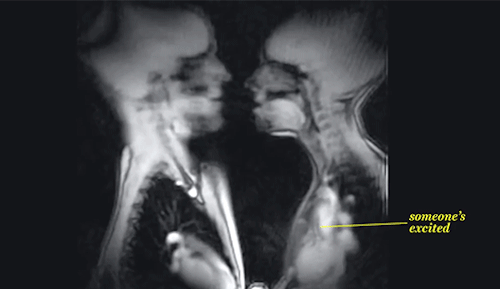

5. Besando, Se puede apreciar la excitación de la persona por el latido de su corazón.